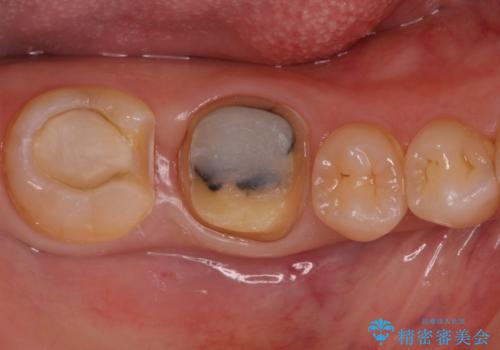

- 右下奥歯の詰め物が取れたとのことで来院されました。

セラミックでの治療をご希望されましたが、残っている歯が少なかったためクラウンでの治療を行いました。

残る歯が薄かったり、十分な量を確保できない場合はクラウンで治療した方が今後の破折リスクを抑えることができます。